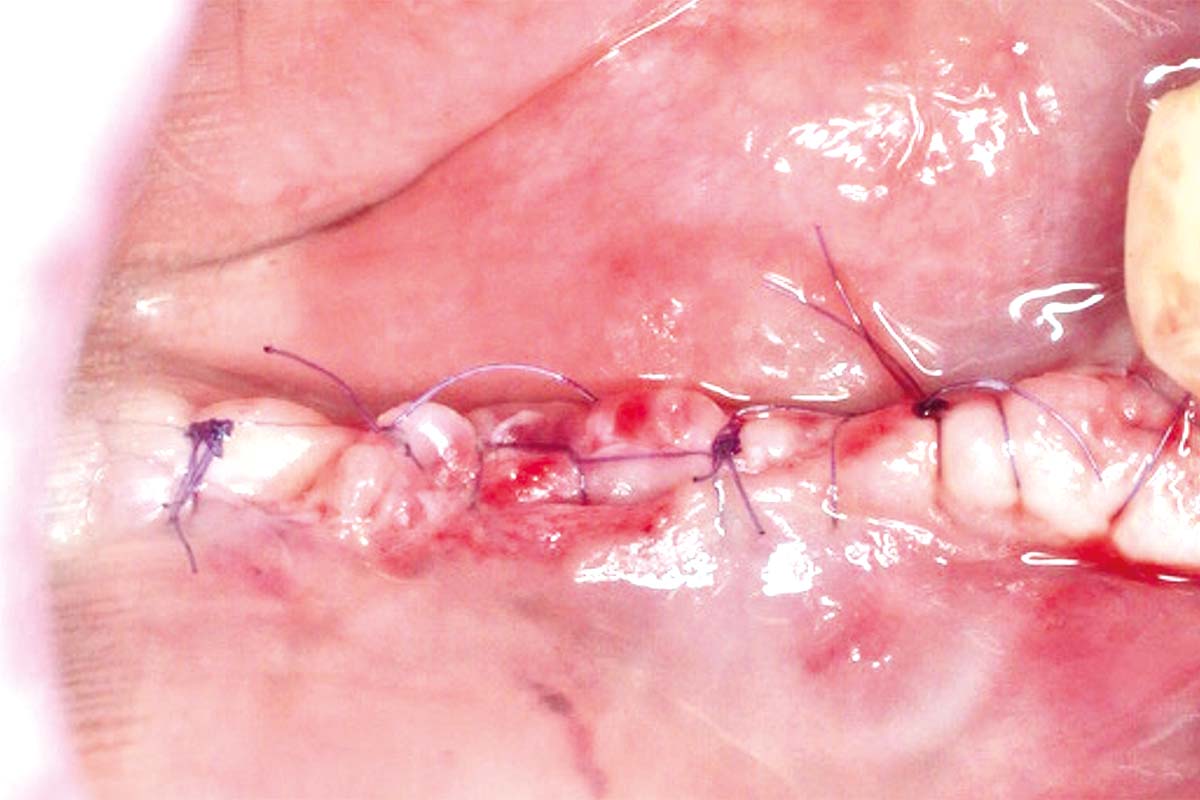

06/10 - Suturing to achieve primary wound closure.

Vertical and horizontal GBR using permamem®, cerabone® and autologous bone - Dr. D. B. Hangyasi